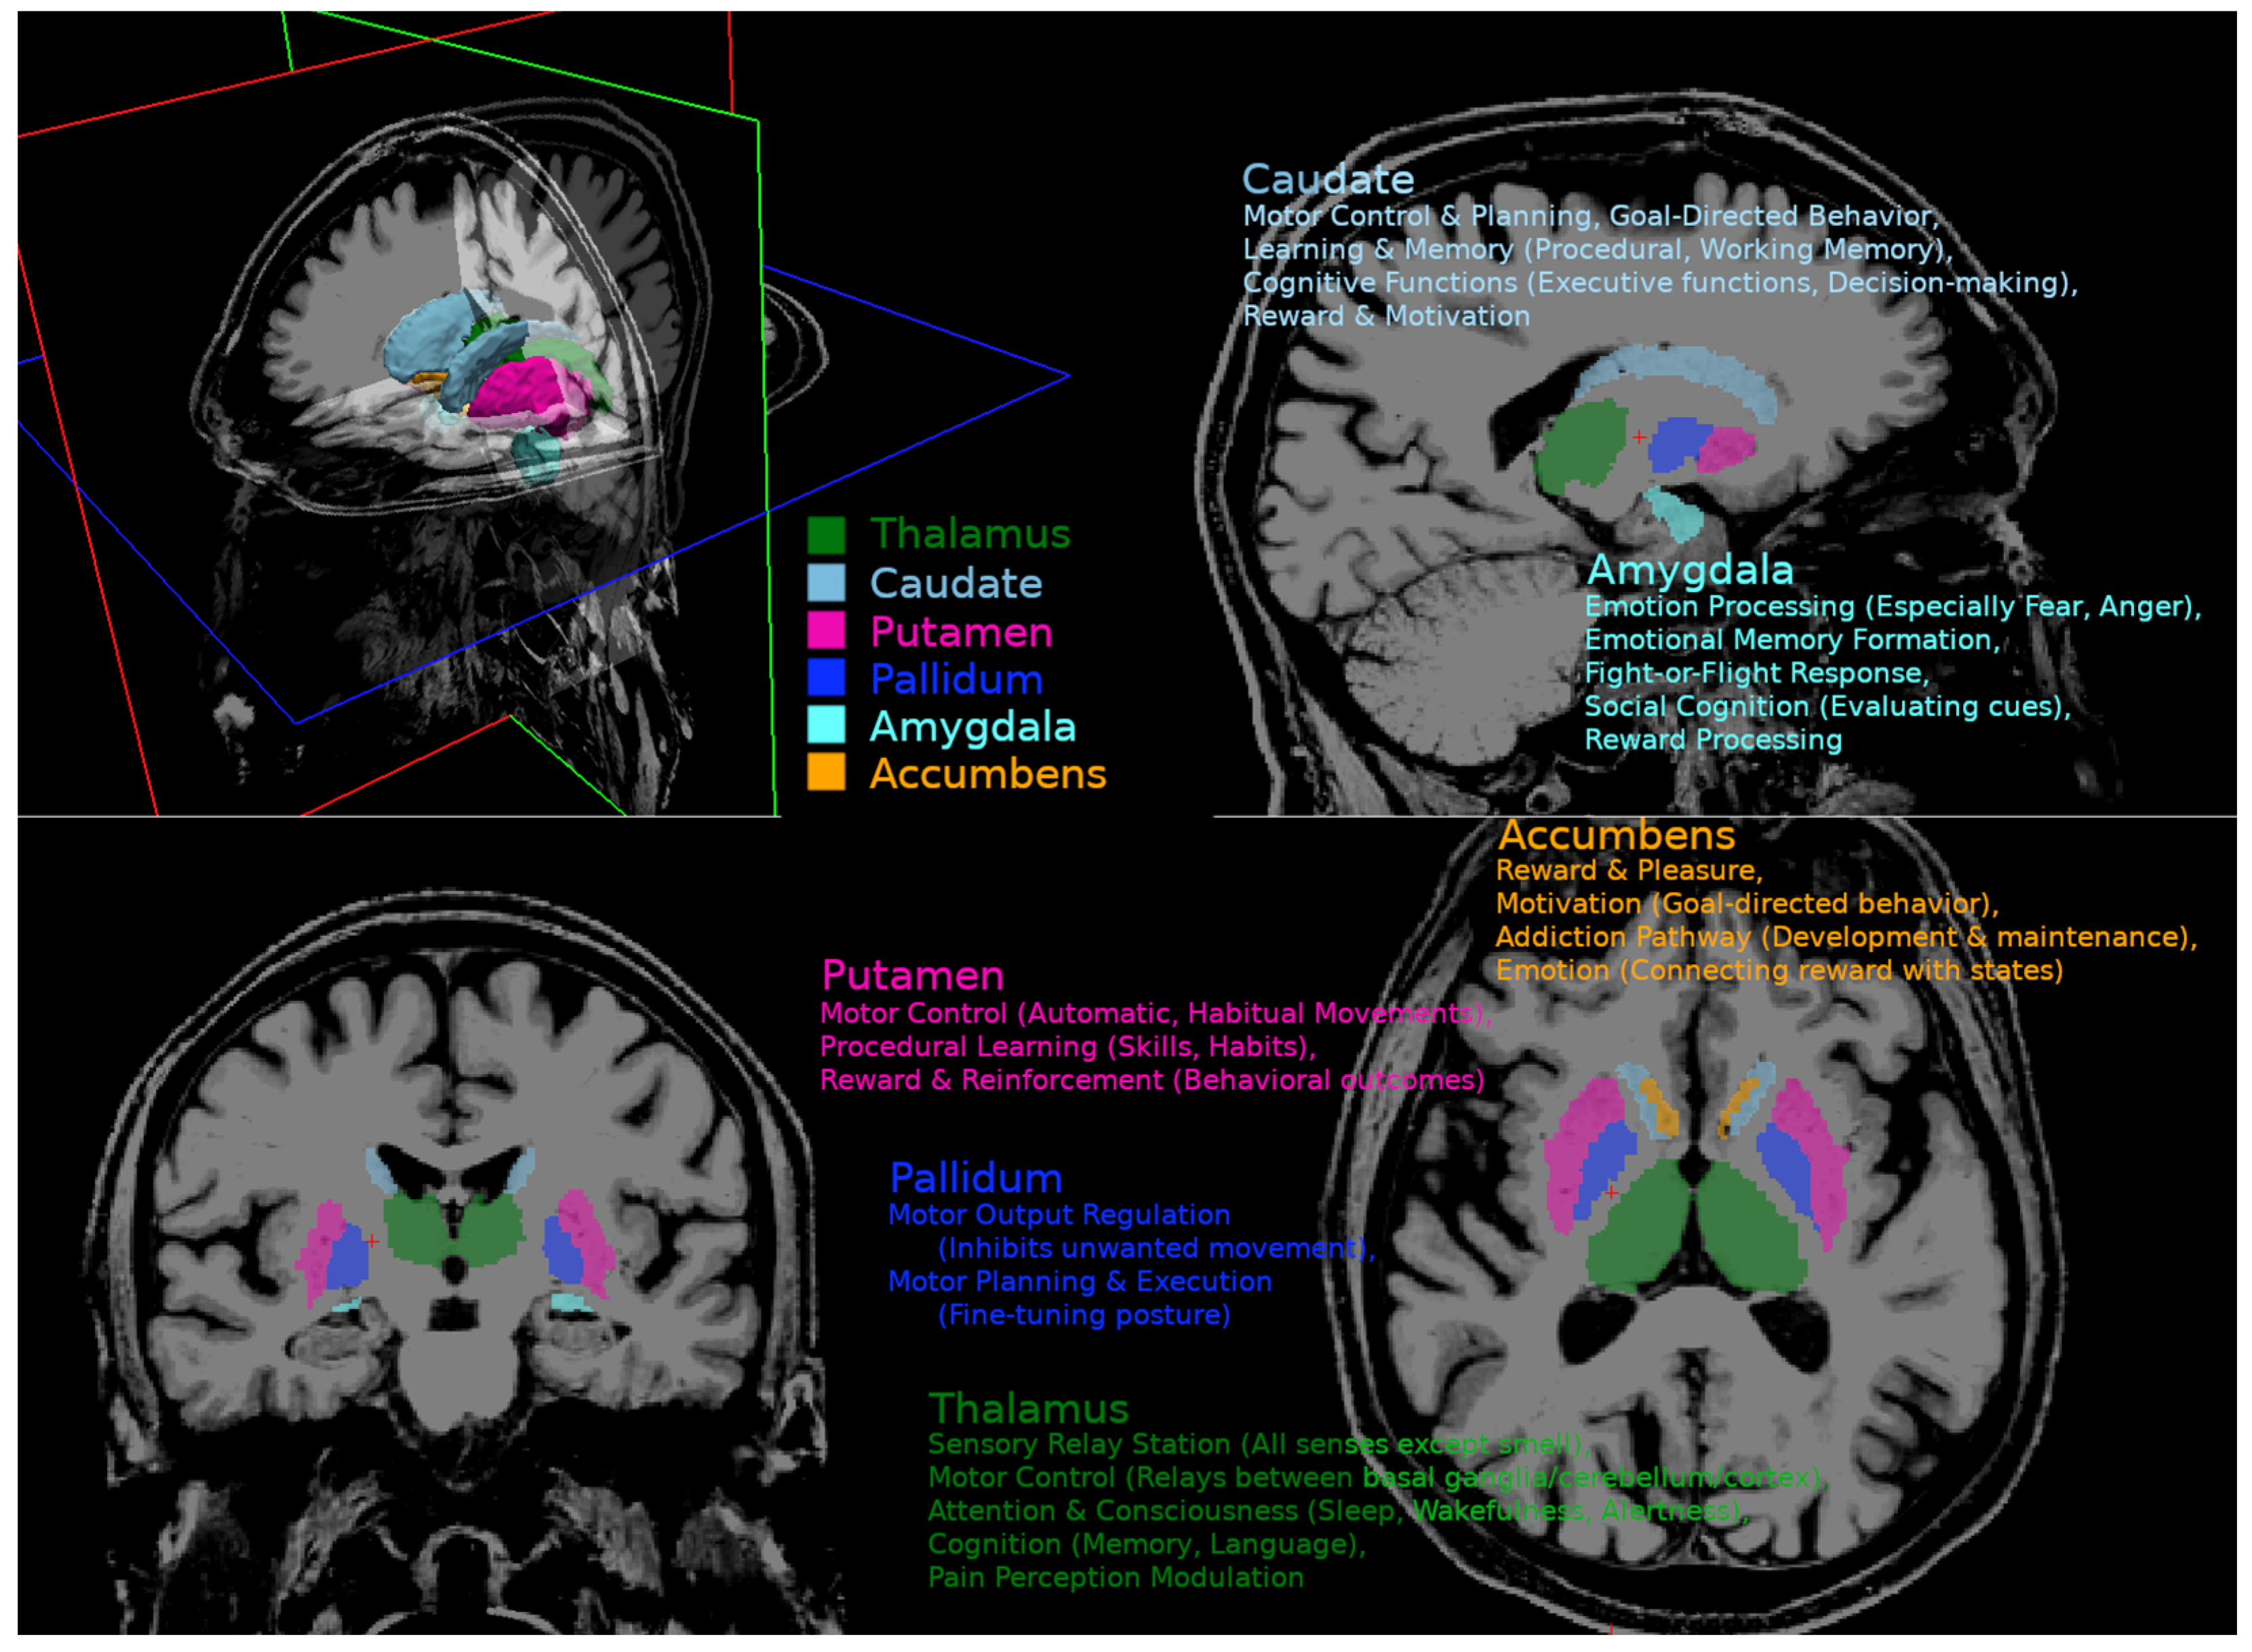

Figure A1. Functional neuroanatomy of the basal ganglia and related nuclei.

Our analysis focused on the deep gray matter regions, as elevated iron levels have previously been found in these areas in cirrhotic patients. We did not assess susceptibility changes in white matter because the counteracting effects of myelin and its orientational dependency hinder clear interpretation. Several methods have been proposed for segmentation of the basal ganglia and thalamus. We employed the multimodal segmentation technique MIST to improve the robustness of the segmentations [22]. MIST combines T1 and T2 contrast and fractional anisotropy (FA) maps to model intensity profiles in multiple images around the boundaries of the structure after nonlinear registration. The advantage of this approach is more robust segmentation, especially in regions where T1 contrast is low. FA maps were calculated from DWI data using the TORTOISE tools [23]. The TORTOISE tool “diff_prep” was applied, using quadratic eddy current correction, ANTSSyN EPI distortion correction, and noise reduction for registration and Gibbs ringing correction. DTI-related metrics, including MD, RD, and FA, were calculated using the tool “diff_calc” from TORTOISE. We focused on subcortical structures involved in cognition, emotion, and motor function, including the globus pallidus, amygdala, CNA, putamen, and thalamus. Graphical presentation of observed regions and their functional involvement is presented in Appendix A. The mean susceptibility of each region of interest (ROI) was calculated using AFNI’s “3dROIstats” program and averaged for both hemispheres [24].